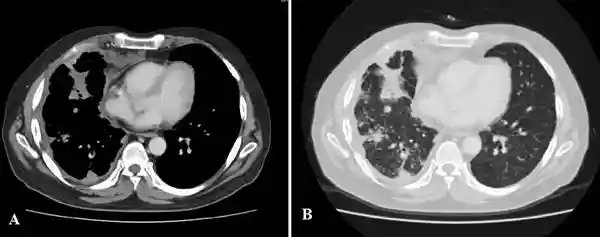

实验室检查显示,白细胞计数13,000/mm3,中性粒细胞占比87.9%。胸部X线显示右肺上叶实变恶化。胸部CT显示右肺疾病进一步恶化,右胸膜间隙积液增多并延伸至胸壁外的右侧胸肌;右肺多发结节,右上肺纤维化(图1)。需与结核病和诺卡菌病相鉴别。

(图1胸部CT检查)